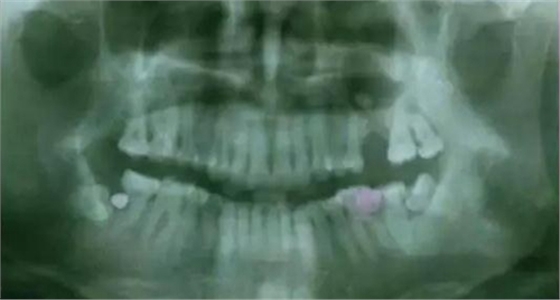

下面看一個(gè)病例,患者,女,30歲,因左下頜智齒嵌塞食物后疼痛,至當(dāng)?shù)匮揽平o予拔除,但術(shù)后1個(gè)半月,患者自覺(jué)拔牙區(qū)一直隱隱疼痛,時(shí)輕時(shí)重,遂來(lái)診。檢查發(fā)現(xiàn),拔牙創(chuàng)口一直未愈合,未見(jiàn)明顯腫脹,拍片發(fā)現(xiàn),拔牙窩內(nèi)顯示高密度斷根影

像,該斷根臨近下頜神經(jīng)管,同時(shí)發(fā)現(xiàn)第二磨牙遠(yuǎn)中有兩塊高密度影像,疑似殘留骨片或牙片,應(yīng)該是引起疼痛的原因,經(jīng)與患者溝通,采納建議,進(jìn)行二次拔牙。

下邊也是一個(gè)斷根病例